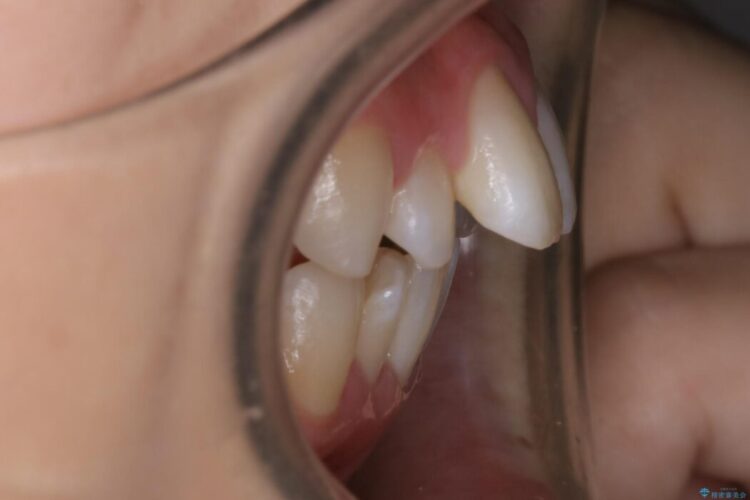

検査したところ歯に対して骨が上顎・下顎共に小さいことがわかりました。

それによりスペースが少なく歯列がガタついたり前方傾斜する生え方となっていました。

本症例の患者様は顎の骨が小さく歯をきれいに並べるための隙間がないため、歯が重なったり傾斜してしまっていました。